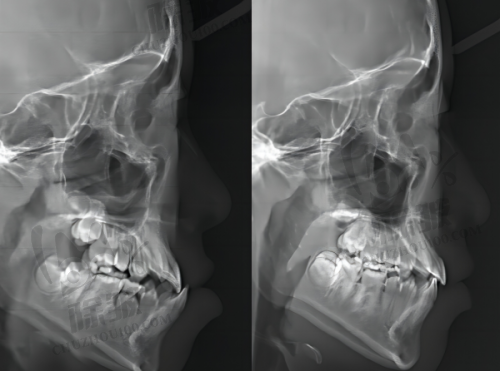

牙贴面是一种覆盖部分牙面的瓷或树脂等材料的修复体。它主要通过粘结技术,将人工修复体固定在患牙表面,以修复牙体的正常形态或改善其色泽。牙贴面的优点有特别多,首先它的磨除牙体组织少,对牙齿的损伤相对较小。与传统的烤瓷牙相比,牙贴面只需要磨除少量的牙齿表面组织,就能达到良好的美容成效。其次,牙贴面的美观度高,尤其是全瓷贴面,它的颜色和透明度与天然牙齿非常接近,几乎可以达到以假乱真的成效。另外,牙贴面的使用寿命也比较长,如果保养得当,可以使用10年甚至更长时间。不过,牙贴面也有一些缺点。比如它的价格相对较高,尤其是进口全瓷贴面;而且牙贴面的边缘可能会出现微渗漏的情况,导致牙齿出现继发龋等问题。所以,在做牙贴面之前,患者一定要充分了解牙贴面的优缺点,根据自己的实际情况做出选择。